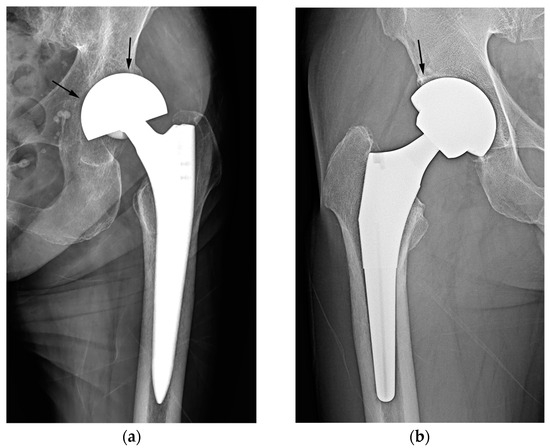

In our study, two cases of THA were erroneously classified as hemiarthroplasty based on the criterion of latitude cut deviation (Figure 7). The boundary of the artificial femoral head could be inaccurately perceived as the cup margin. Historically, femoral heads ranging from 22 mm to 28 mm in diameter have been predominantly used for THA. However, recent advancements in bearing materials have enabled the use of thinner liner designs, thereby allowing the accommodation of larger artificial femoral heads. Along with the theoretical advantages associated with larger femoral heads, this has spurred the adoption of femoral heads with diameters ranging from 36 mm to 40 mm for THA. When a sizable femoral head aligns with the anteverted acetabular cup contour, it can bewilder readers lacking familiarity with hip implants. This perplexity may lead to a misinterpretation of the cup margin and implant outline. To mitigate this confusion, adhering to the principle of drawing a chord line that links the two points where the silhouette deviates from the outer sphere contour could facilitate a precise estimation of the latitude cut.

Figure 7.

A simple radiograph after THA showing that the margin of the artificial femoral head (arrow) was confused with the margin of the cup by the raters. Adhering to the principle of determining a chord line that connects the points where the silhouette diverges from the outer sphere contour can facilitate an accurate estimation of the latitude cut.